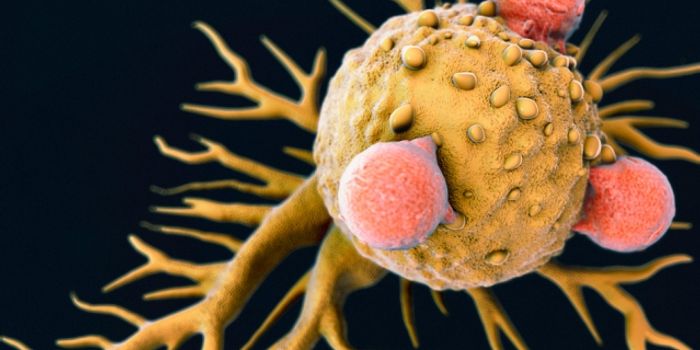

JAN 23, 2018ImmunologyScientists propose extracting dendritic cells and priming them to fight cancer before returning them to a patient as par ...

NOV 13, 2018ImmunologyPancreatic Cancer is a devastating disease. Fifty-five thousand new patients were diagnosed this year in the United Stat ...

MAR 27, 2023CancerInnate Immunity is a nonspecific host defense mechanism against foreign antigens. It is the first line of defense in a h ...